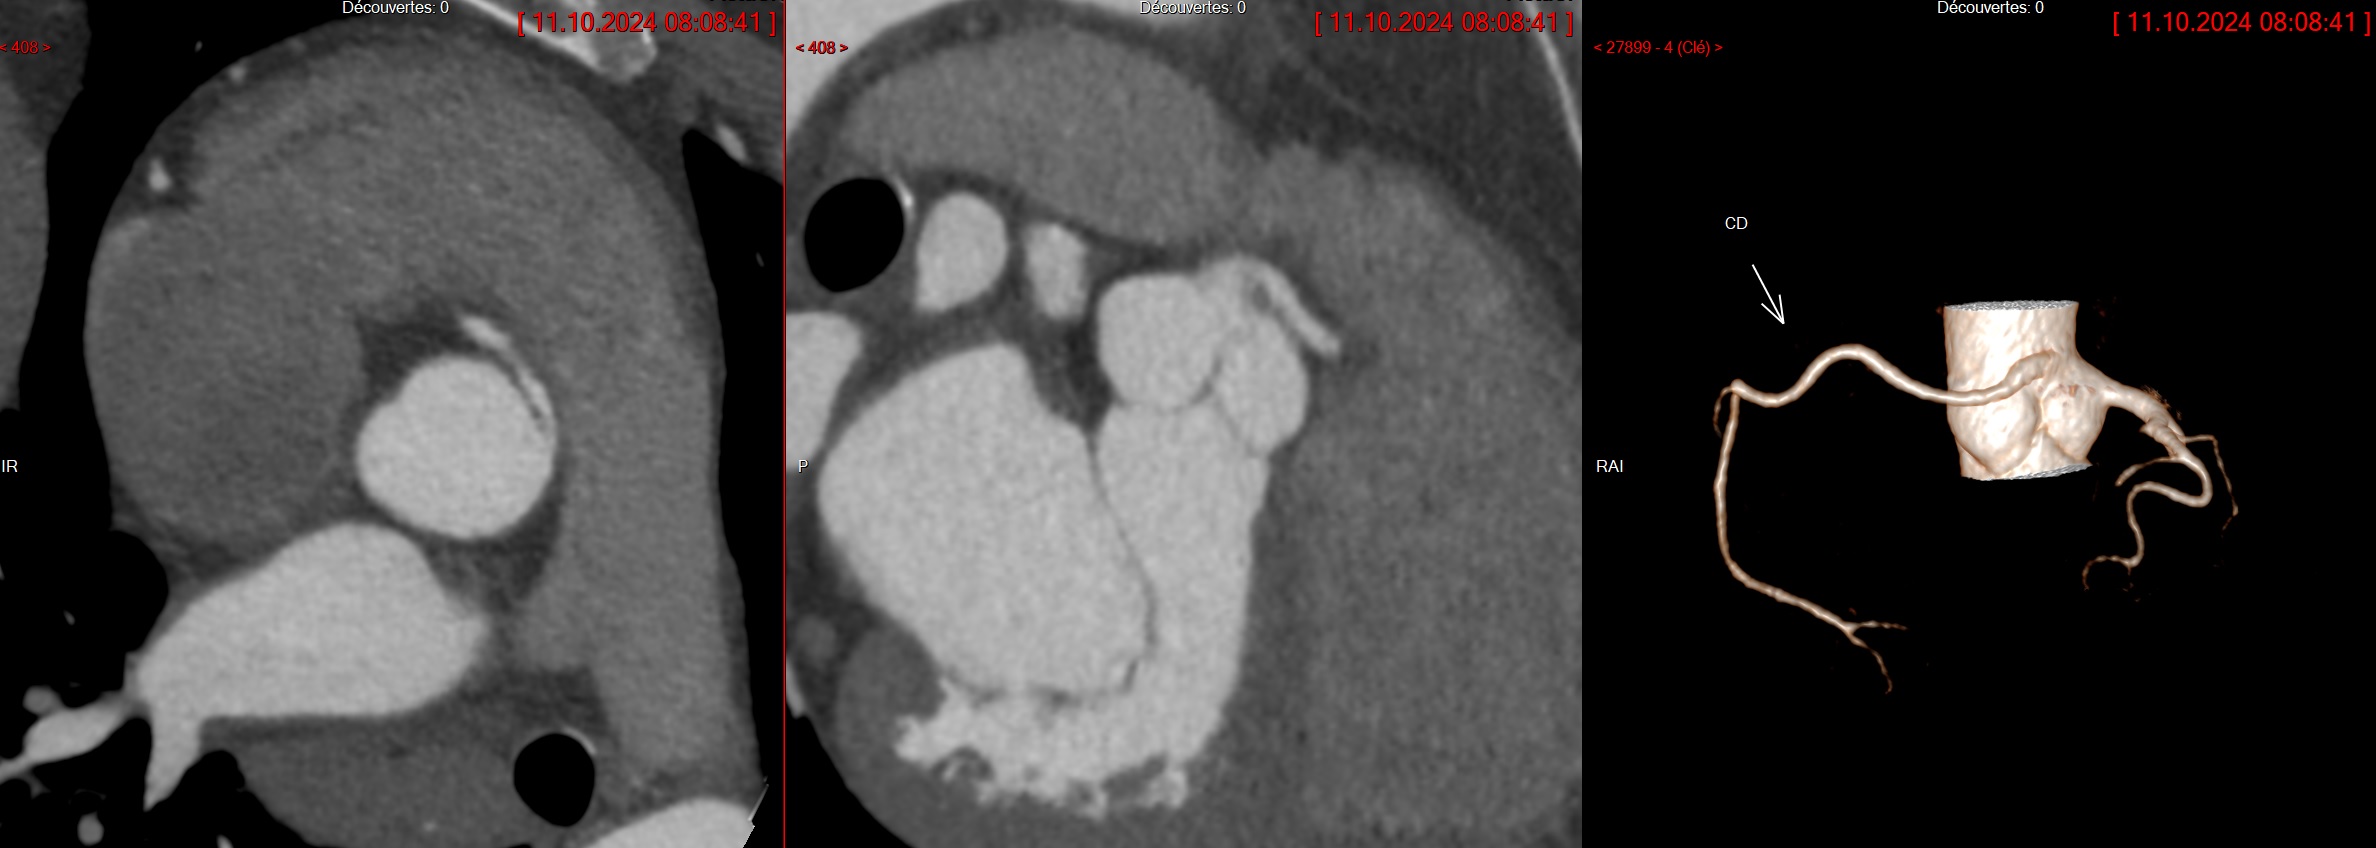

Cas

Coronaire droit

Depart CD et CG du sinus de valsalva droit, passant devant le tronc pulmonaire

Depart CD et CG du sinus de valsalva droit, passant devant le tronc pulmonaire

Trajet malin de la CD avec départ haut situé

Trajet malin de la CD avec départ haut situé